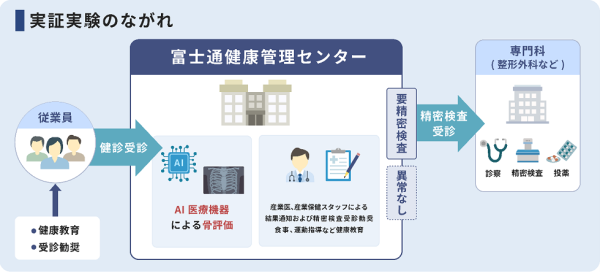

本実証実験では、iSurgeryのAI医療機器「医用画像解析ソフトウェア Chest Bone Indicator」(注5)(以下、AI医療機器)を活用し、富士通グループの従業員向け健康診断の受診者に対して、胸部X線写真から骨の状態を評価し、結果を通知する。評価結果に応じて専門医、精密検査の受診を勧奨するほか、評価結果にかかわらず東京慈恵会医科大学が提供する骨の健康に関する基礎知識を活用して、予防のための健康指導なども行う。

これらの施策の結果、従業員の骨粗しょう症の予防や健康に関する意識向上、ならびに健康のための行動の変化につながったかをアンケートなどにより把握し、企業による従業員向け骨の健康増進施策の有用性を検証する。

本実証実験では、富士通グループの従業員向け健康診断の受診者の胸部X線写真をAI医療機器で分析し、骨評価を行う。富士通の産業医、産業保健スタッフは従業員に骨の状態の説明や健康指導、教育、健康指導をし、健康行動に移すことを促す。骨の状態によっては、受診・精密検査を勧奨する。これらを受けた従業員の健康意識・健康行動の変化をアンケートなどにより測定し、企業が従業員向けに行う骨の健康増進施策の有用性を検証する。また、本プロジェクトで得られたデータを骨粗しょう症の有病率、骨粗しょう症検査の要精密検査率などの国内外の疫学データと比較して医学的な妥当性を検証し、胸部X線写真の活用による骨評価の有効性を学術的にまとめる。

・AI医療機器よる骨の状態評価と結果の通知

・骨の状態評価結果に基づく受診・精密検査の勧奨

・ビデオセミナー、食事指導、栄養指導

・行動変容ステージに関するアンケート、精密検査受診者の受診結果(骨粗しょう症の有無、骨密度測定結果)の確認および検証

富士通:健康診断実施主体として、検査、結果通知の実施体制の構築、運営。健康診断実施後の教育、健康指導の実施。

iSurgery: AI医療機器の提供および適切な実施体制の構築の支援、食事、運動指導の情報の提供。

東京慈恵会医科大学:十分な臨床的・学術的意義の検証のための専門的な助言、および骨に関する基礎知識や予防方法などのビデオセミナー、食事指導・運動指導の情報提供、学術発表。